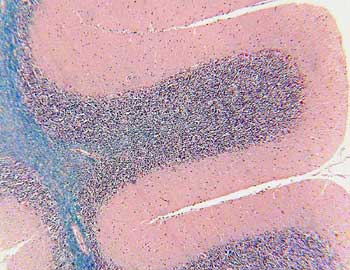

Cerebelo (Luxol Fast Blue) |

Visión general:

a pequeño aumento se distinguen las hendiduras cerebelosas en

la superficie del órgano con restos de tejido meníngeo,

delimitando las más pequeñas o también llamadas

hendiduras terciarias los elementos básicos de la laminilla cerebelosa.

La sustancia blanca forma el eje de la laminilla, de color azulado,

y la gris la porción periférica de dicha estructura, con

un color más rosa/azul.

Visión específica: a mayor aumento podemos

delimitar en la sustancia gris y de superficie a profundidad las tres

capas arquitecturales: capa molecular o superficial, capa de las células

de Purkinje o intermedia y capa de los granos cerebelosos o profunda.

En íntimo contacto con esta última nos encontramos con

la sustancia blanca, rica en fibras nerviosas y células gliales.

En la capa molecular, en contacto con la superficie meníngea

veremos escasas células neuronales y gliales con abundante neuropilo.

La capa de células de Purkinje se distingue por los grandes somas

piriformes neuronales de citoplasma eosinófilo y núcleo

redondeado con nucléolo evidente que en ocasiones muestra la

salida del gran tronco dendrítico en dirección a la capa

superficial. La capa de los granos es densamente celular con elementos

redondeados neuronales de pequeño tamaño con escaso neuropilo.

Por último la sustancia blanca está constituida por fibras

nerviosas y celularidad escasa glial formando el eje de la laminilla

y el tronco del cerebelo, y por contener fibras mielinizadas se tiñe

de color azul.